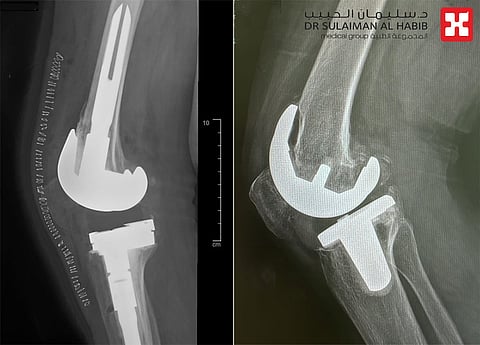

وأوضح د. القحطاني أن الفريق الطبي أخضعها لفحوصات طبية دقيقة، أهمها الأشعة المقطعية لاختبار جودة العظام وكثافتها، والتأكد مما إذا كانت مصابة بالهشاشة أم لا، وغيرها من الفحوصات التي بينت وجود تخلخل وانحراف في المفصل، مع تآكل العظم، وتلف الغضاريف.

واستطرد د. القحطاني الحاصل على الزمالة الكندية للإصابات الرياضية وجراحة المناظير واستبدال المفاصل، قائلاً أن المراجعة أخضعت لعملية جراحية معقدة تم فيها استخراج المفصل الصناعي القديم، واستبداله بآخر نوعي مخصص لمثل هذه الحالات، كما تم وضع دعامات لتثبيت المفصل، مشيراً إلى أن العملية مضت بصورة سلسلة ووفقاً للخطة العلاجية، وتكللت ولله الحمد جهود الفريق الطبي بالنجاح، إذ عادت المريضة للمشي على قدميها بصورة طيبة بعد العملية مباشرة بمساعدة أخصائي العلاج الطبيعي، قبل أن تغادر المستشفى بعد أيام بحالة جيدة.